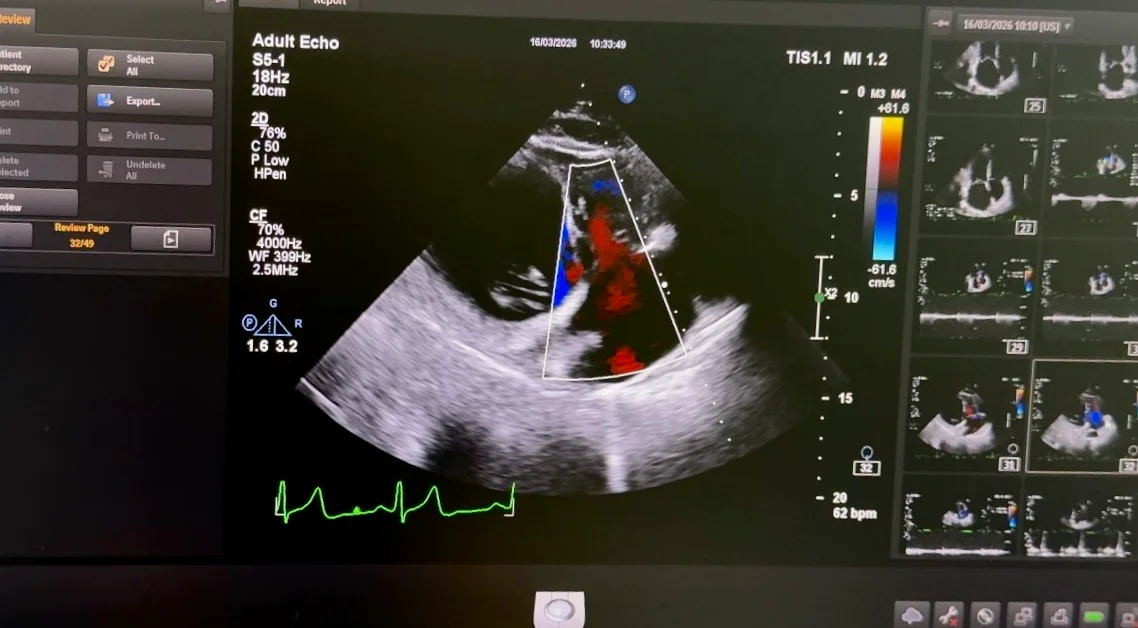

Потік регургітації є розсіяним: він поширюється під передню та задню стулки, формуючи значний об’єм зворотного потоку (див. фото 2).